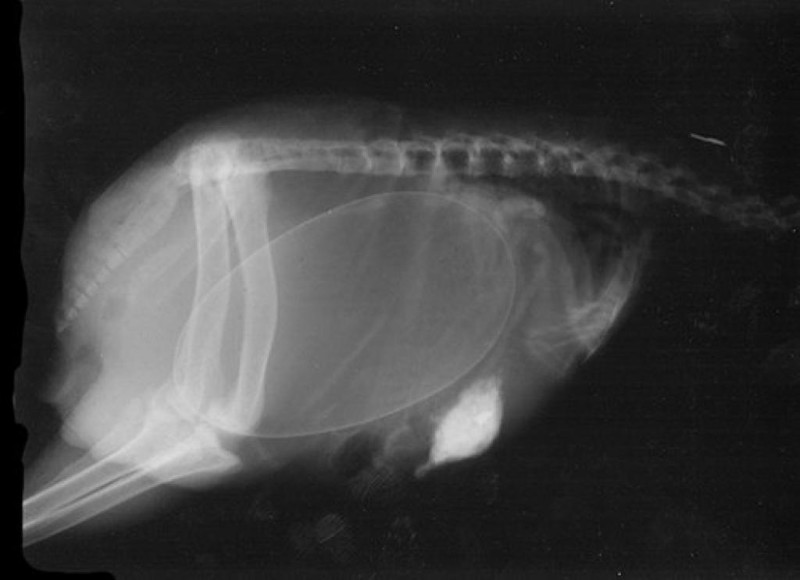

Մենք բոլորս լավ պատկերացնում ենք, թե ինչպես է անցնում մարդու հղիությունը, և շնորհիվ ժամանակակից տեխնոլոգիաների՝ կարող ենք տեսնել երեխային մայրիկի արգանդում հղիության ամենավաղ փուլում։ Իսկ ինչպե՞ս է ընթանում կենդանիների հղիությունը։ Մասնագետները, ովքեր հոգ են տանում հղի կենդանիների մասին, ներկայացրել են նրանց ռենտգենային և ուլտրաձայնային լուսանկարները, որոնք ձեր դատին է հանձնում «twizz.ru» կայքը։

Կրիա